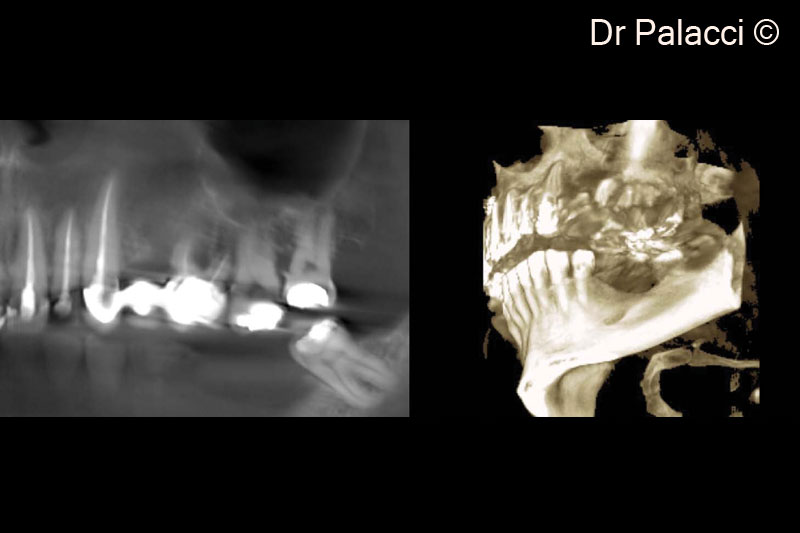

Hình ảnh X-Quang minh họa sự nâng cao sống môi